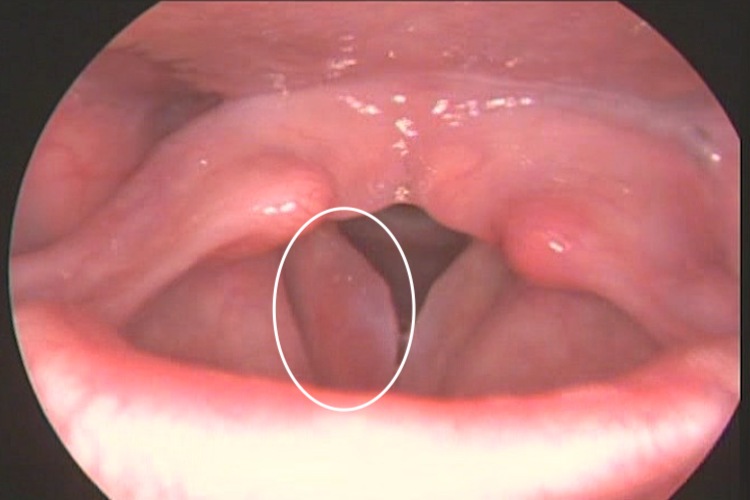

声带水肿是指声带黏膜下有组织液浸润,通常发病迅速,主要表现为声音嘶哑、喉部有异物感、吞咽困难,若水肿波及喉部者,则有呼吸困难、喘鸣、呼吸音重浊现象。喉镜检查可见杓会厌皱襞肿胀如粗腊肠形,会厌部也可出现肿胀。